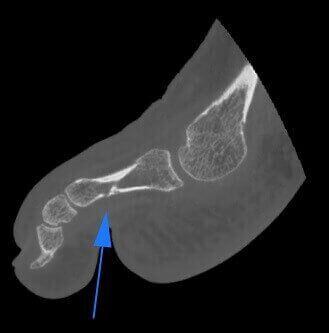

Frattura di osso sesamoide

Frattura di osso Sesamoide e Falange